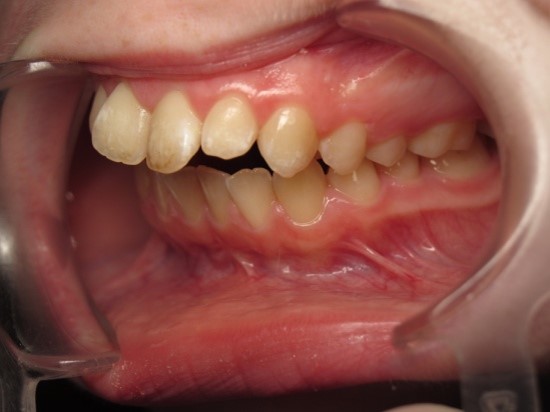

Pic.22. Tortoocclusion of teeth 11 and 21, open bite.

Pic.23. Tortoocclusion of teeth 11 and 21, prognathic, cross bite.